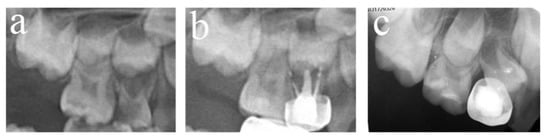

Figure 3.

#84 was treated with pulpectomy and filled with ZOE under DGA. The follow-up period was 34 months (31-month-old male child) (a) Two weeks after the operation, the radiographic showed that the filling in the distal roots was underfilled. (b) Thirty-four months after treatment, #84 was lost early, but a portion of the ZOE particles remained. The pulpectomy in #84 failed.